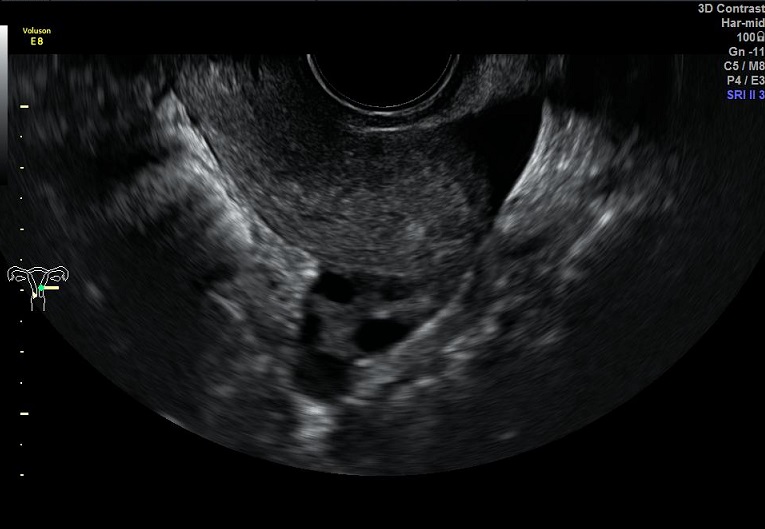

女性,30岁,继发性不孕2年,左侧输卵管宫外孕术后。常规二维超声子宫、卵巢及宫腔三维均未发现明显异常。宫腔置管后,宫腔水造影显示:宫腔稍见膨隆,内膜面光整,推注时有阻力。子宫输卵管实时三维超声造影显示:左侧输卵管未显示,右侧输卵管近端纤细,远端稍膨大,走行呈“S”行弯曲。诊断:左侧输卵管不通,右侧输卵管通而不畅。